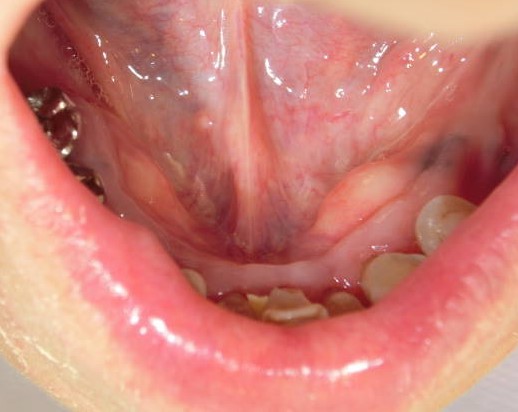

(1)口蓋隆起 torus palatinus

(2)下顎隆起 torus mandibularis